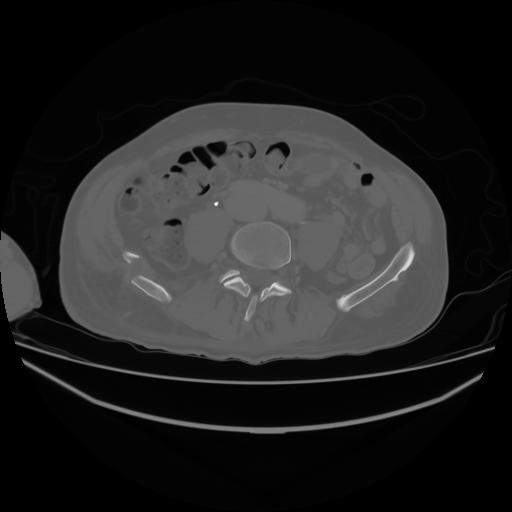

4 CUERPO,CE,Axial,3.0,CUERPO,,